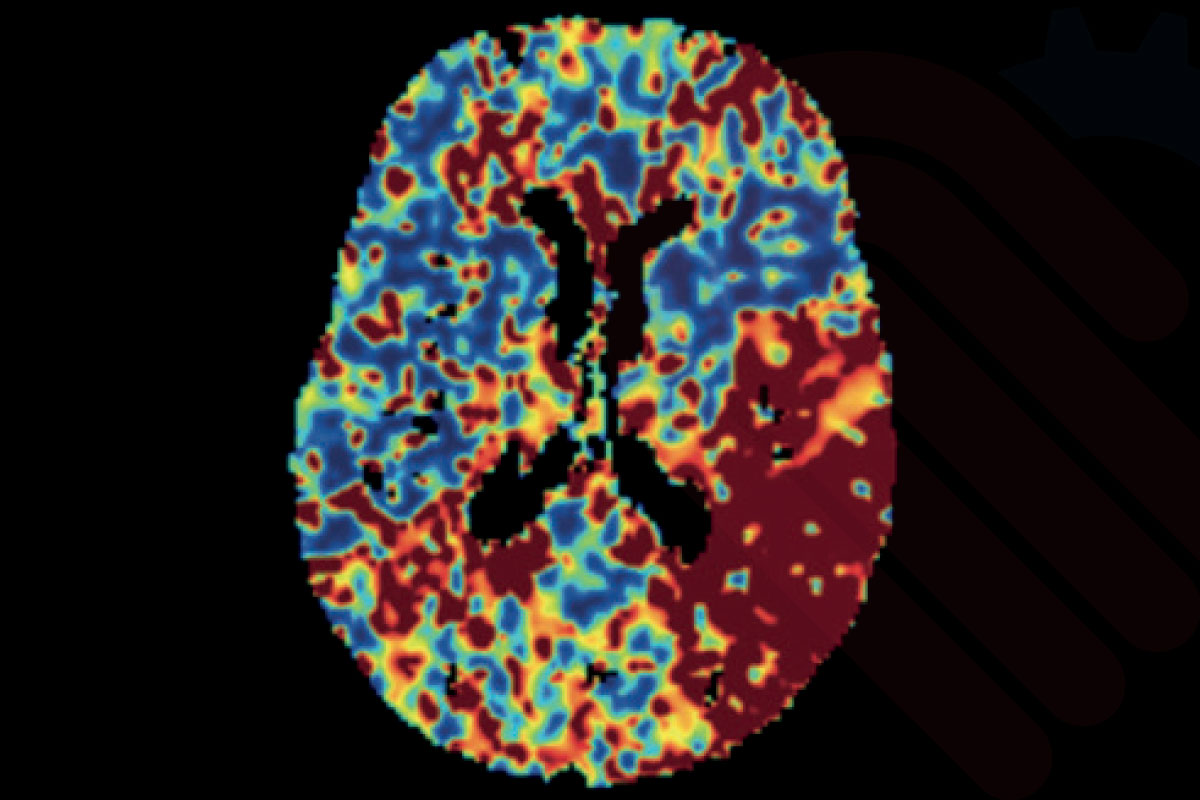

Beyin görüntülemelerinde AI destekli analiz ve raporlama çözümleri, görüntü verilerinin hızlı ve tutarlı şekilde değerlendirilmesine yardımcı olur. Bu yaklaşım, klinik karar destek süreçlerini güçlendirerek zaman kritik hasta yönetimine katkı sağlar.